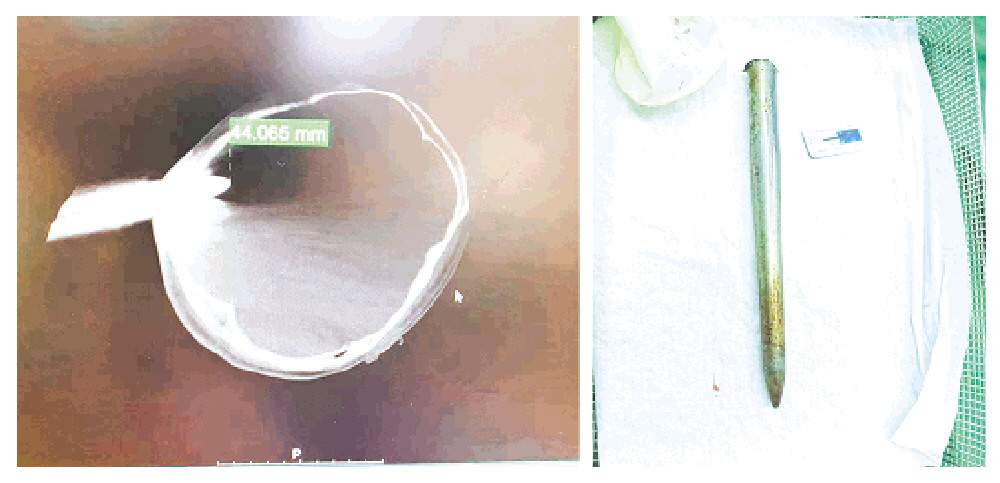

小桂到院后,医院立即启动创伤救治绿色通道。影像检查提示:钢枪位于右侧颞顶部交界区,导致右侧颞骨、顶骨骨折,枪尖深入脑组织约1.5厘米,引发颞叶脑组织挫伤出血及少量硬膜下血肿。最为凶险的是,钢枪尖端距离颅内横窦仅约0.5厘米,且受金属伪影干扰,部分血管显示不清,手术风险极高,犹如在“雷区”排雷。

手术室内,在气管插管全麻成功后,手术团队切开头皮显露术野,继而小心翼翼地围绕钢枪周边1厘米处用铣刀锯开颅骨,最后成功将骨瓣与钢枪一并平稳取出。手术历经2小时40分,术中出血仅100毫升。